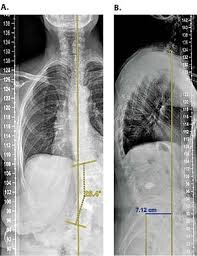

I'm reaching the age where my bones should become more and more stiff. As you already know, I have Scoliosis from bad posture and such. How can I change this? Perhaps some supplements with training at home? Is MK-667 recommended?

I'm also interested in height gain as I believe that I have a couple centimeters tucked away in my spine.